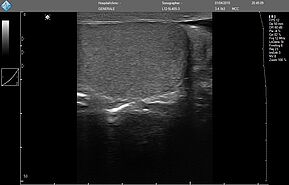

MicUs Pro доступен в 3 версиях:

- MicrUs Pro-L40S (линейный, 5-12 МГц, 40 мм)

MicrUs Pro-L40N (линейный, 5-12 МГц, 40 мм, производительная версия)

MicrUs Pro-C60S (конвексній, 2-5 МГц, R60 мм)